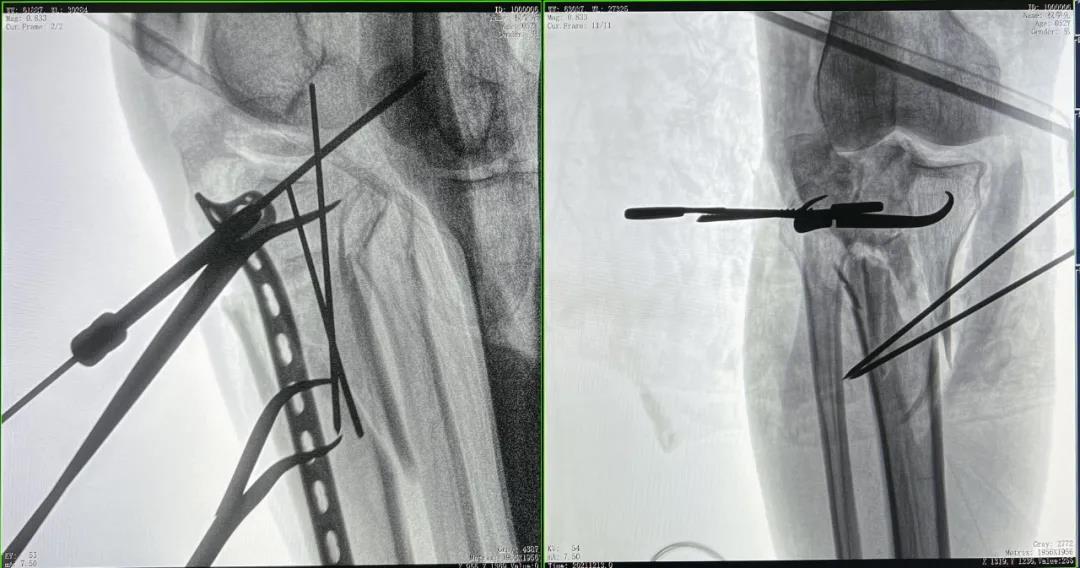

患者2:男性,52歲,脛骨骨折切開復(fù)位鋼板內(nèi)固定術(shù)

術(shù)前CT三維重建影像可見脛骨平臺處粉碎性骨折

優(yōu)質(zhì)的術(shù)中影像輔助螺釘準(zhǔn)確植入